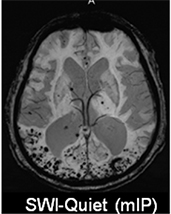

◆高分解能(高画質)な画像 Head MRA, SWI 局所励起

[頭部撮像症例]

“SWAN”(T2 Star Weighted MR angiography)

SWANは、3D高速グラディエントエコー法にマルチエコーの収集を組み合わせたパルスシーケンスです。ヘモジデリンの沈着による磁場の乱れを画像化するアプケーションで、主に頭部領域における微小出血の検出などに有効な撮像法です。